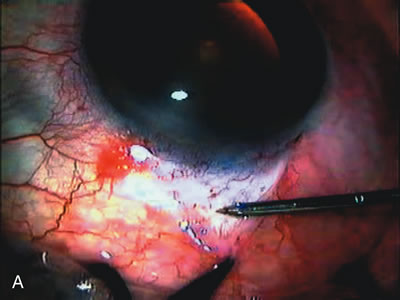

Fig. 7. Phacotrabeculectomy adjacent to a failed filter in cataractous eye. The ability to combine small-incision cataract extraction with trabeculectomy all through the same incision adjacent to the failed filter allows the surgeon to work in a familiar superior area. Avoiding incisions into the existing bleb decreases conjunctival buttonholes, hypotony, operating room time, and subconjunctival bleeding. A. Appearance of failed bleb with exposure of superior temporal quadrant gained with a corneal traction suture. B. Prepare a limbus-based conjunctival flap and a scleral flap. C. This bleb is at high risk to fail again justifying the need for MMC, 0.2 mg/cc applied on a pledget for 4 minutes. D. Insert the keratome and perform phacotrabeculectomy in the usual fashion.